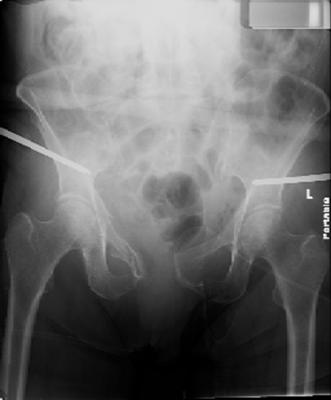

attached are images of a 70 year old female after peds versus car. her own car ran her over.

injuries are limited to the pelvis. left rami open and visible in a 10cm vertical laceration just lateral to left labia majora. wound is grossly clean. no vaginal and no urinary issues. CT scan shows widening of both SI joints anteriorly but I think this is vertically stable pattern.

pt treated that night with I/D and supra-acetabular frame to close the ring. consideration was given for SI screws bilateraly, but given time of night and other factors decision made not to proceed.

so the question is what next operatively if anything? concerns are infection, nonunion anteriorly and possible incompetence of the pelvic floor which may lead to prolapse

issues. right rami are comminuted and plating may entail ilioinguinal approach to extend plate laterally to right iliac wing. retrograde screw up right rami is an option but I am not convinced it will add much. adding SI screws very doable, but major concern is restoring anterior ring. so far wound is clean and closed over a drain, and I have no plans to open it back up and wash again.

maintaining pelvic alignment in ex-fix in 70 yo female for any length of time may be challenging.

any thoughts? would anyone plate the pubic symphysis to close the gap and leave the more lateral rami fractures alone? the most recent pelvic case on this website involved pts with suprapubic catheters and antibiotic options including resorbable beads. I wonder how many people would plate and place antibiotic beads. thanks.